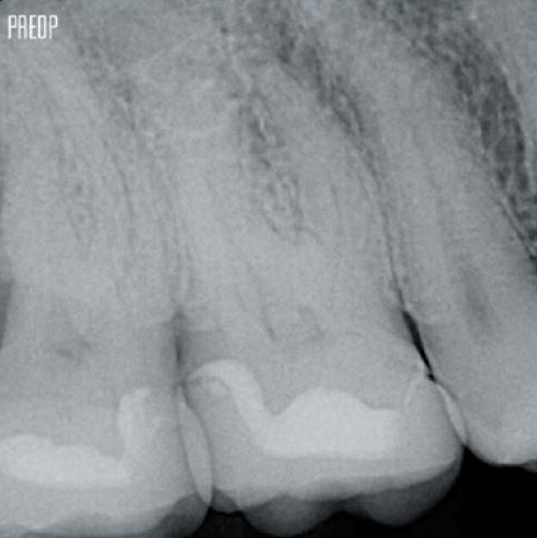

Photos avec l’aimable autorisation du Dr Ahmed Salman